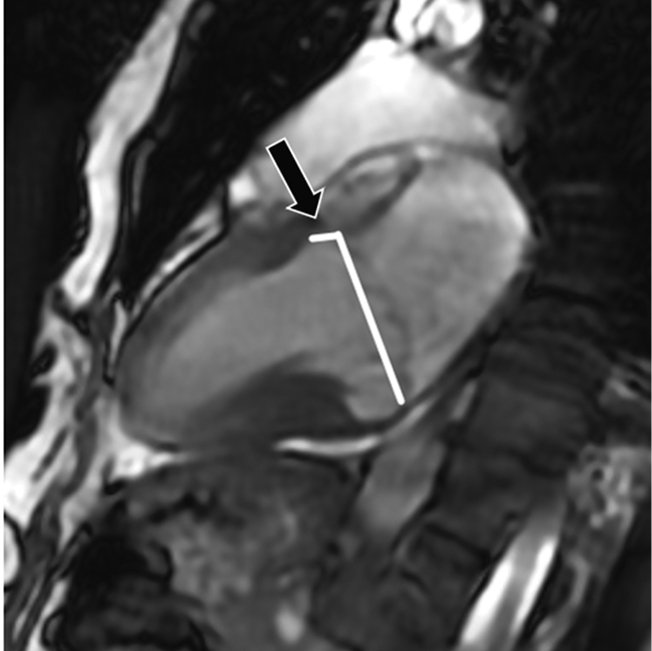

The distance from the base of the mitral valve fibrous annulus to the upper contour of the LV myocardium was measured on end-systolic cine images. The MAD extent at the level of the posterior and anterior mitral valve leaflets was measured along the three-chamber and long LV axis, respectively. The MAD extent was 11 mm and 5 mm unde the posterior and anterior leaflets, respectively (Fig. 5, 6).

Fig. 5. Left ventricular three-chamber axis, cine end-systolic image. Measurement of the mitral annular disjunction distance for the posterior mitral valve leaflet. Mitral annular disjunction is indicated by an arrow